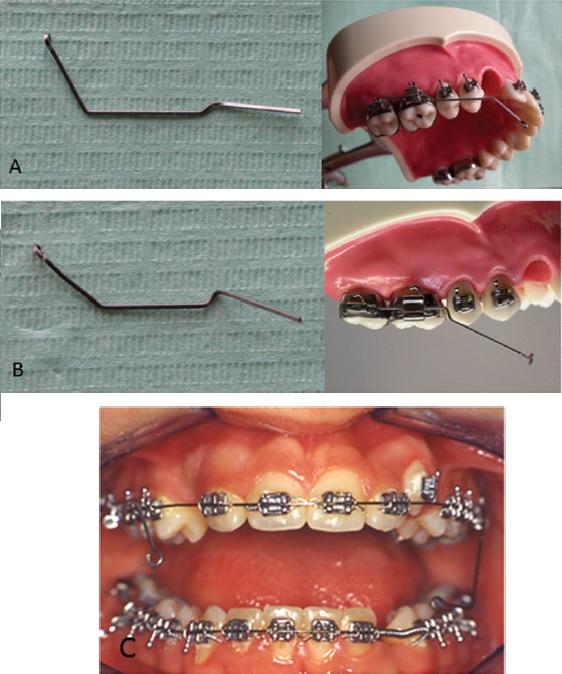

Дентальная галерея: ретинированный зуб клык и его лечение

Раздел: Компас решений